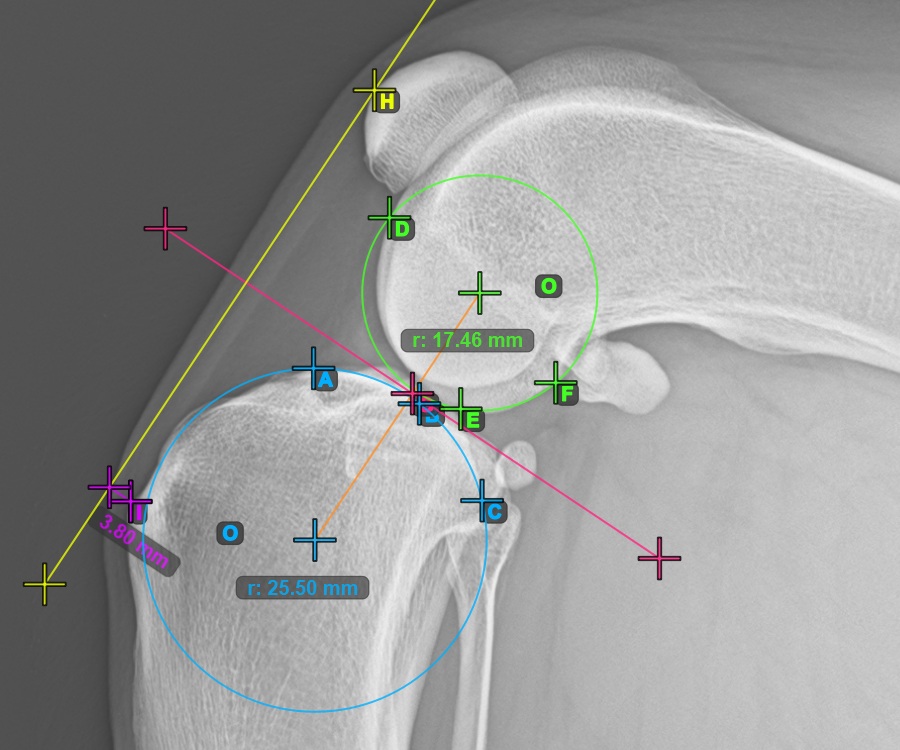

Jelöljön meg egy pontot az ízület előtt a két kör közötti közös tangensen. Egy vonal automatikusan áthalad a megjelölt ponton.

A lenti kép a két kör közötti közös tangensen elhelyezett pont tipikus elhelyezkedését ábrázolja.

Kezdje el a TTA mérés eljárást a Patella legfelső pontjának megjelölésével.

A lenti kép a Patella legfelső pontjának szokásos elhelyezkedését ábrázolja.

A TTA mérés TTA - 1 Condylus változatának befejezéséhez jelölje meg a Crista Tibiae (Tuberositas Tibiae) legdorsalisabb pontját. A Tuberositas Tibiae és a Patella legfelső pontja mentén húzott vonal közötti távolság adja meg a szükséges beállítást a TTA eljáráshoz.

A lenti kép a tibia tuberositásának, a tibia taraj legkiemelkedőbb pontjának szokásos elhelyezkedését ábrázolja.